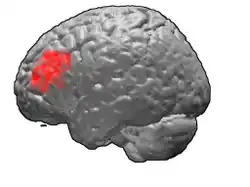

Brodmann area 46, or BA46, is part of the frontal cortex in the human brain. It is between BA10 and BA45.

BA46 is known as middle frontal area 46. In the human brain it occupies approximately the middle third of the middle frontal gyrus and the most rostral portion of the inferior frontal gyrus. Brodmann area 46 roughly corresponds with the dorsolateral prefrontal cortex (DLPFC), although the borders of area 46 are based on cytoarchitecture rather than function. The DLPFC also encompasses part of granular frontal area 9, directly adjacent on the dorsal surface of the cortex.